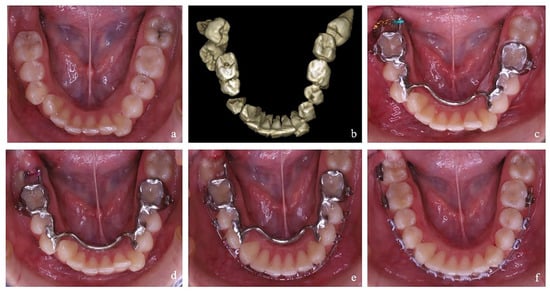

Figure 2. Preoperative Imaging and Intraoral scan: (a) Patient STL file showing the occlusion (a-1) and lower dental arch (a-2); (b) CBCT scans: (b-1) before surgical manipulation; (b-2) after the healing period following extraction of the mandibular third molars and placement of orthodontic buttons with traction chains on the impacted mandibular second molars, temporarily bonded to the buccal surface of the mandibular first molars.

The clinical protocol included patients diagnosed with mandibular second molar (MM2) impaction, confirmed via cone-beam computed tomography (CBCT). Three-dimensional imaging enabled precise assessment of the position of the impacted teeth as well as the presence and location of the developing third molars. In addition, digital intraoral scans of the upper and lower dental arches and their occlusal relationships were performed to generate a complete digital model of the oral cavity, as shown in Figure 2. Intraoral and extraoral photographs were also obtained as part of a comprehensive orthodontic analysis, along with supplementary diagnostics to evaluate the overall orthodontic condition.

Particular attention is given to refining the traction vector for impacted mandibular second molars (MM2), as this determines the location of the anchorage point in the forthcoming digital construct. Tooth movement commonly begins with buccal Figure 2 or lingual uprighting, followed by distal crown tipping. Analysis of the planned traction vector determines the PDaA design and the choice of surgical approach for third-molar extraction and second-molar exposure.

In clinical practice, two surgical–orthodontic techniques are recognized: (1) Closed technique: The third molar is extracted, the second molar is exposed, and a button (or chain) is bonded; the surgical site is then primarily closed. The chain emerging from the wound is passively secured to the adjacent teeth (the first molar or the second premolar) Figure 2(b-2). After a healing period, the orthodontist places the PDaA and actively engages the chain to initiate traction of the impacted MM2. (2) Open technique: This may be performed in one or two stages. In the two-stage approach, the third molar is extracted; following a healing period with osseous fill of the retromolar space, the impacted second molar is exposed, and the site is covered with a surgical dressing. After approximately three days, the orthodontist fixes the PDaA to the mandibular anchorage teeth and begins traction. More commonly, we prefer a single-stage approach in which the third molar extraction and second molar exposure are completed in one session, followed by placement of a surgical dressing. On postoperative day 3–4, the pre-fabricated PDaA is delivered, an attachment (button or traction chain) is bonded to the impacted second molar, and traction is initiated.